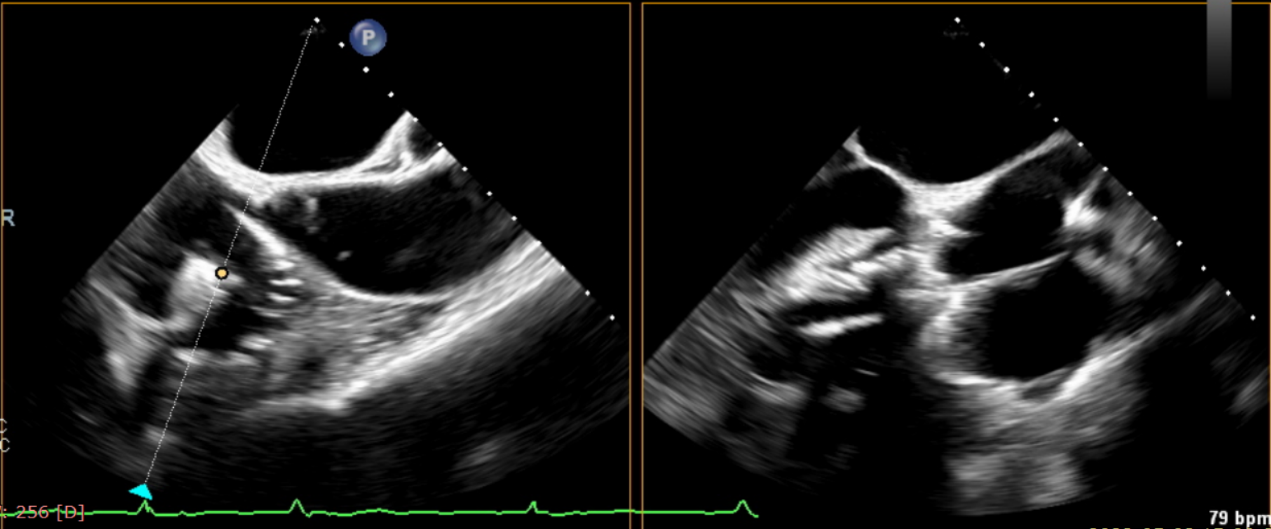

術(shù)后超聲提示無瓣周漏